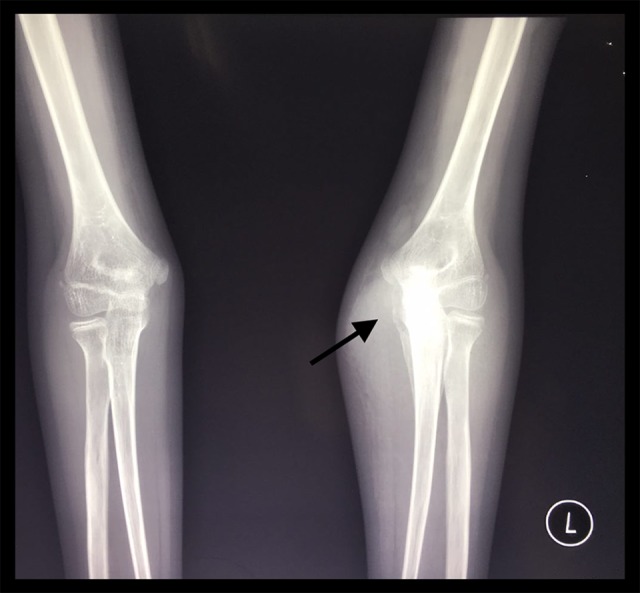

Figure 5.

X-ray of the left elbow showed osteomyelitis of the proximal left ulnar (arrow).

Upon admission, the patient’s vital signs were normal. She had normal body mass index (BMI) with short stature (height < −2 SD on the World Health Organization [WHO] growth standards [5]), her weight was 23 kg. The cervical lymph nodes were palpable, 0.5–1 cm in diameter, multiple, soft, bilateral, and non-tender. The lumps were 10×8×8 cm, 2×2×1 cm, and 3×3×2 cm in size, on the elbow, hand, and foot, respectively. The lumps on the foot and hand looked swollen and red with tenderness on palpation, while the lump on the elbow was not painful nor red. Blood work at the time of admission was within normal limits. Liver function test, namely aspartate aminotransferase (AST) 28 U/L and alanine aminotransferase (ALT) 18 U/L were within normal limits (normal reference value at our institution for AST: 35 U/L; ALT: 45 U/L). From the clinical findings, we made differential diagnosis of extrapulmonary TB (joint, bones, and skin) and bacterial infection, most likely staphylococcal or other mixed bacteria. Tuberculin skin test was 12 mm in induration. GenXpert result from induced sputum yielded no detected M. tuberculosis. Chest x-ray revealed pulmonary TB with lymphadenopathy on the right supra-hilar (Figure 4). X-ray of the hand and elbow showed an osteomyelitis of the proximal left ulnar (Figure 5) and 5th metacarpal of the left hand, with a spina ventosa depiction on the 5th meta-carpal (Figure 6). Fine needle aspiration biopsy (FNAB) of the lumps suggested a chronic inflammation caused by TB. Human immunodeficiency virus (HIV) test was negative.